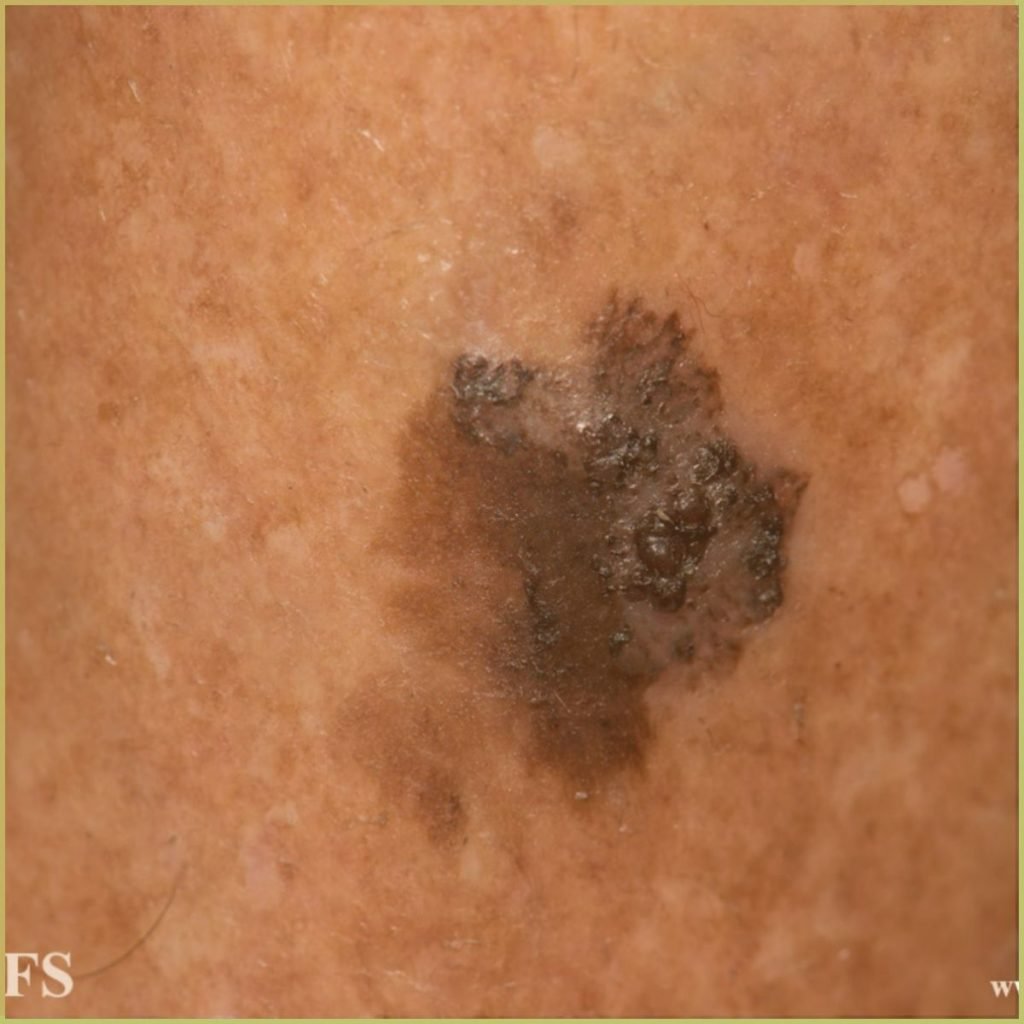

MELANOMA

Melanoma refers to a highly aggressive tumor that develops from cutaneous melanocytes derived from the neural crest cells in the basal layer of the epithelium. Oral malignant melanoma is an extremely rare malignancy. It has a higher tendency to metastasize to underlying tissues and a relatively low (<20%) 5 year survival rate. Risk factors for mucosal malignant melanoma include alcohol consumption, tobacco use, and denture irritation. The common clinical presentation includes:

- Early lesion – pigmented macular patch with irregular borders.

- Mature lesion – deeply pigmented nodular lesion with possible ulceration.

Diagnosis is based on the lesion history, clinical presentation and microscopic findings, which may include:

- Atypical melanocytes (hyperchromatism and nuclear pleomorphism)

- Advanced lesions may include infiltration into lamina propria and muscle.

- Positive immunohistochemical markers (S-100, HMB-45, fatty acid synthase).